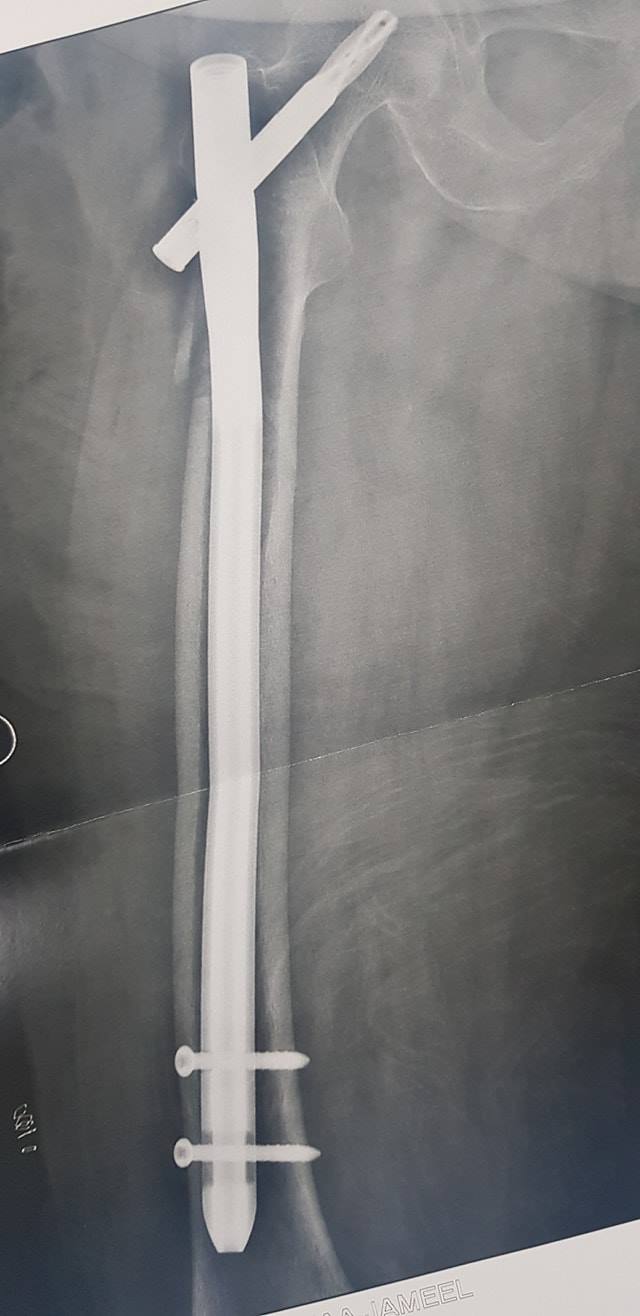

كافة انواع الكسور وعلاجها